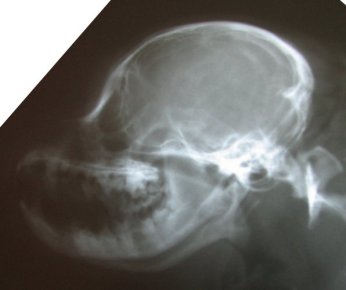

The skull x-ray of a dog with a full cerebellum is below that on

the left and the skull x-ray of a dog with a crushed cerebellum

is shown on the right. You can easily see there is a distinct

difference in the shape of the back of the skull between the two

and why the cerebellum ends up crushed. The most distinct

difference, besides the fact that the skull on the right is

shorter from front to back, is that the occiput sticks out in

the skull x-ray on the left. In the right, that occiput is still

there, but it is more downsloped and blends in with the back of

the skull to the point you can barely see it--almost like

someone took a hammer to the occiput and smashed it in.